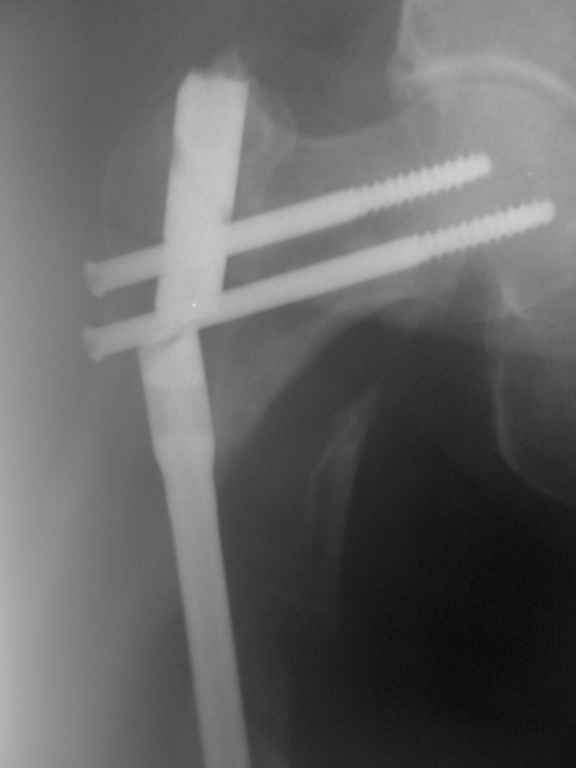

первичные Р-гр

|